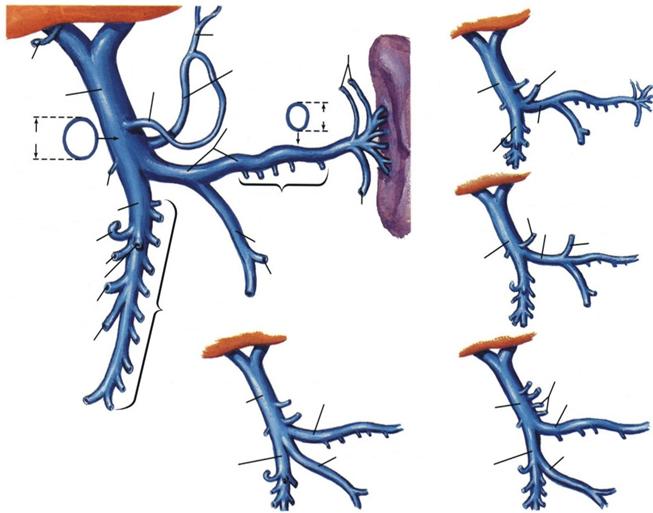

Vena porta aduna sangele venos din intreg tubul digestiv subdiafragmatic, din glandele anexe ale acestuia si splina, ducandu-l la ficat

vena porta hepatica situata vena porta se poate deschide vena pulmonara se poate strictura congenitala a

anterior de capul pancreasului in VCI (arterele hepatice deschide in vena porta venei porte hepatice

si prima parte a duodenului apar marite) hepatica

v.esofagiana

v.cistica v.gastrica v.gastrica stanga v.gastrica stanga

dreapta

vena porta vena porta

0,45 cm

vena

E

1,09 cm splenica

VMI

v.gastroepiploica stanga v.splenica

v.gastroepipl.dr. VMI v.gastrica stg

vena porta

v.pancr-duod inf.

D

v.colica medie v.colica stanga

v.colica dreapta vv.jejunale

si ileale

v.ileocolica

vv.intestinale inalte

A

vena porta v.lienala vena porta v.splenica

A = dispozitie tipica (45%)

B = VMI se varsa in unghiul format de

varsarea VMS in v. lienala (30%)

C = VMI se deschide in VMS (25%)

D = v. gastrica stanga se varsa in

v. lienala (24% din cazuri)

E = v. gastrica stanga se varsa in un-

ghiul format de VMS si v. lienala

VMS

VMI VMI

B C

VARIANTE ALE VENEI PORTE